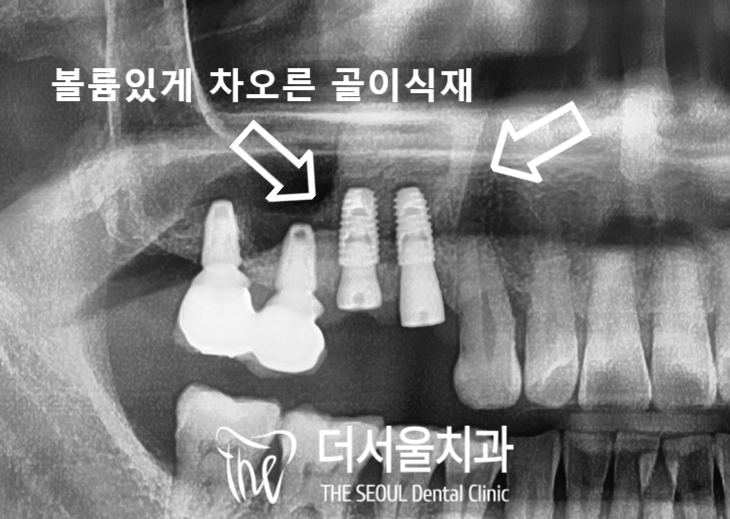

상악동은 ‘빈 공간’ 이며

이곳이 얇은 막으로 감싸져 있습니다.

뿌리쪽을 들여다 봤을 때

어둡게 보여지는 ‘염증’ 들도 관찰되었죠.

이런 병소들이 점점 퍼져나가면서

뼈를 녹여서 두께가 얇아진 것입니다.

뿌리 끝이 어두워져 있는 것이 확인되죠?

이것들을 그대로 두면

주위로 계속 퍼져나가게 됩니다.

뼈 이식재는 혈액과 만나게 되면

골 융합 과정을 거치게 되며

엑스레이로 확인을 했을 때에

하얗게 보여집니다.